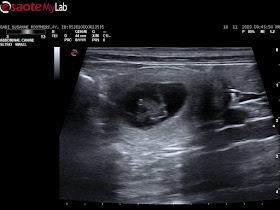

Mandag den 18-11-2019:

Gabi skulle scannes, det var dag 27/28.

Gabi er med hvalpe. Kathrine kunne se 7 hvalpe.

Det er så vildt - Vi kan næsten ikke tro det.

Men vi glæder os såååå meget.